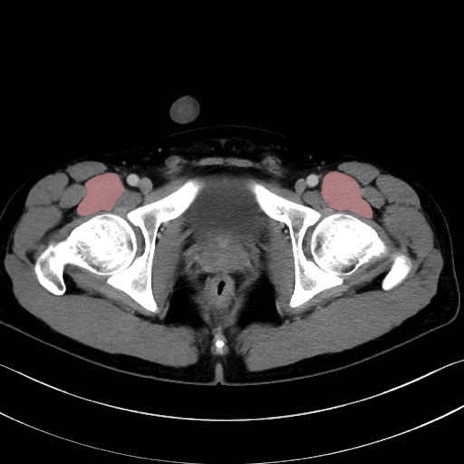

腸骨筋 (Iliacus)